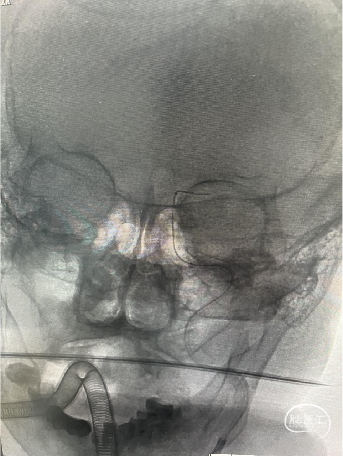

DSA:左侧颈内动脉C4段闭塞。

侧支循环评估:

DSA:通过左侧大脑前动脉软膜支、左侧大脑后动脉软膜支少量代偿。